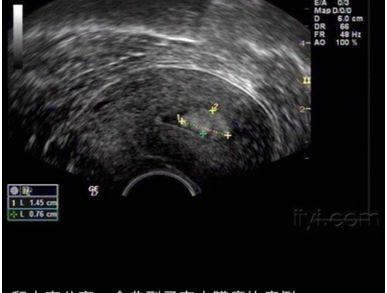

子宫内膜息肉

超声是妇产科的主要辅助检查手段,某些疾病的早期,在超声表现不典型,不可能替代病理,遇到超声提示:内膜回声不均时应该警惕以上情况的出现,可以诊断性刮宫送病理结 合宫腔镜检查还要结合临床及其他检查,进一步明确诊断。同时不要紧张,因为有一部分是正常的,如:药物流产后,子宫内膜没有来得及修复,这种情况是正常的,也可见于使⽤外源性雌激素药物等。